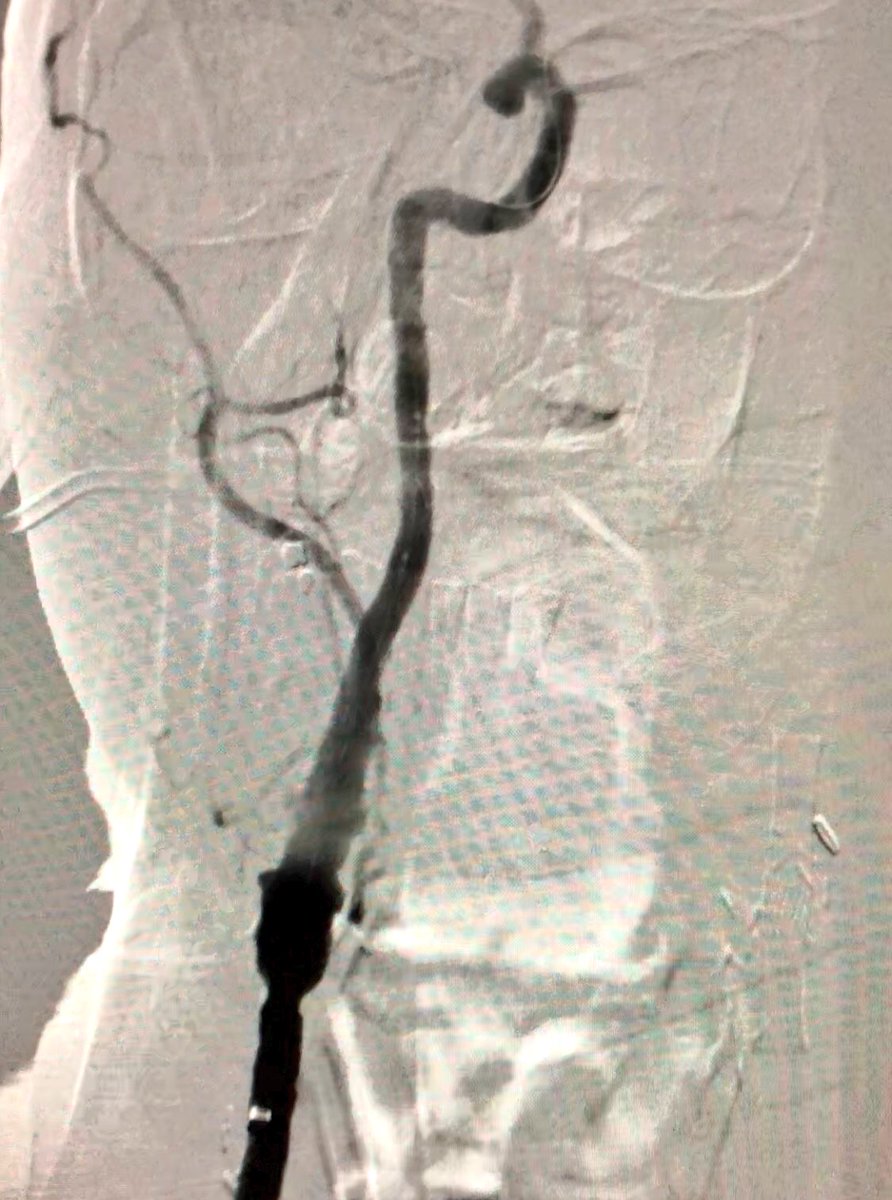

56 y/o WM with symptomatic R CCA/ICA disease, previous CEA. Carotid artery stenting planned via #RadialFirst approach but converted to ulnar based on vessel size by ultrasound #SCAIPAD